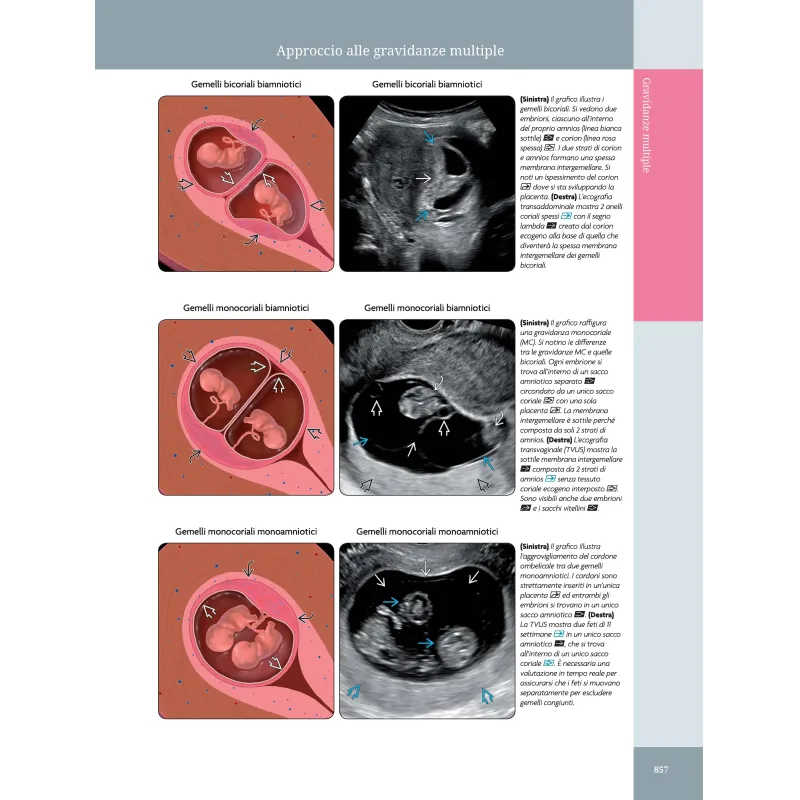

Ostetricia. Diagnostica per Immagini rappresenta una valida risorsa nel campo della diagnostica per immagini ostetrica. Grazie alla curatela di Gianluigi Pilu e alla traduzione di Elena Brunelli, Josefina Diglio e Anna Seidenari, questa edizione italiana basata sulla quarta edizione in lingua inglese, mantiene l'eccellenza accademica e professionale degli autori originali Paula J. Woodward, Anne Kennedy e Roya Sohaey. L’opera si distingue per la sua capacità di fondere la ricchezza visuale con contenuti scientifici di alto livello, offrendo una guida completa sulle più moderne tecniche di imaging in ostetricia. Il libro affronta ogni aspetto dell'ecografia ostetrica, dalle anomalie congenite maggiori e minori alle sindromi e ai disordini multisistemici, passando per la diagnostica delle gravidanze multiple e le condizioni materne che influenzano la gravidanza. La presentazione dell'edizione italiana sottolinea l'importanza di un testo stampato in un'epoca dominata dal digitale, valorizzando l'esperienza di lettura tradizionale senza rinunciare all'innovazione. Questa edizione, infatti, è arricchita da un'impeccabile qualità delle immagini e da una grafica di prestigio, rendendola uno strumento indispensabile non solo per gli specialisti del settore ma anche per la formazione di nuovi professionisti. La prefazione sottolinea gli sforzi collaborativi di un team di esperti, che hanno lavorato per portare ogni capitolo al massimo livello di eccellenza, con l'obiettivo di migliorare la diagnosi e la comprensione delle patologie fetali. Con oltre 5.000 immagini e video, questa risorsa si impone come una delle più complete disponibili sul mercato per chi si occupa di imaging ostetrico.